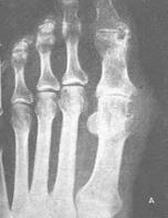

痛风诊断方法

实验室检查:1.尿液检查 正常人经过5天的限制嘌呤饮食后,24h尿的尿酸排泄量一般不超过3.57mmol(600mg)。由于急性发作期尿酸盐与炎症的利尿作用,使患者的尿尿酸排泄增多,因而此项检查对痛风的诊断意义不大。但24h尿…